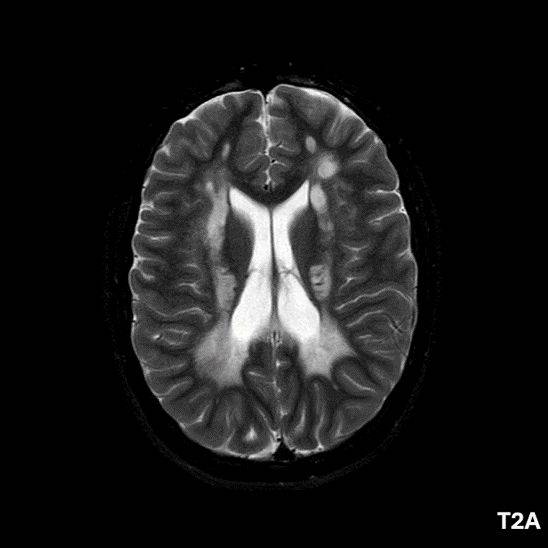

- A) Aksiyel T2A ve koronal T2A sekanslarda sentrum semiovale, korona radiata ve bazal ganglionlar düzeyinde bilateral frontoparietal derin periventriküler beyaz cevherde birleşme eğilimi gösteren hiperintens gliotik sinyal değişiklikleri (oklar) ve aksiyel T2A serilerde servikal spinal kordda posterior kolonda, lateral kesimlerde sinyal artımları (oklar) izlendi.

- B) Kontrastsız T1A serilerde tarifli alanlarda hipointens (oklar) görünüm izlendi. Kontrastlı T1A serilerde bu düzeyde (oklar) kontrastlanma artışı izlenmedi. Diffüzyon ağırlıklı serilerde belirgin diffüzyon kısıtlaması (oklar) görülmedi.

- LBSL, karakteristik radyolojik özelliklere sahiptir. MRG’de tipik olarak bilateral ve simetrik beyaz cevher sinyal değişiklikleri görülürken, subkortikal U lifleri, internal kapsülün posterior kolları, trigeminal sinir traktları, serebellum, korpus kallozumun spleniumu, medulla oblongata ve omurilikteki dorsal kolonlar ile lateral kortikospinal traktlar genellikle korunur.

- Etkilenen bölgelerde T1’de hipointens, T2/FLAIR’da hiperintens sinyal değişiklikleri izlenir. DWI’de lezyonların periferinde kısıtlı difüzyon görülebilir. MRS’de beyaz cevherde laktat artışı saptanabilir, ancak bu her hastada mevcut değildir.